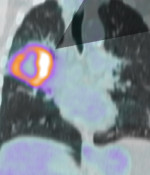

Clinicopathologic and metabolic variables from 18F-FDG PET/CT in the prediction of recurrence pattern in stage I-III non-small-cell lung cancer after curative surgery.

G. Jiménez-Londoño, J. Pérez-Beteta, M. Amo-Salas, A. Honguero, V M. Pérez-García, C. Lucas, A. M. Soriano, A. M. García-Vicente

Annals of Nuclear Medicine 9 (2025)